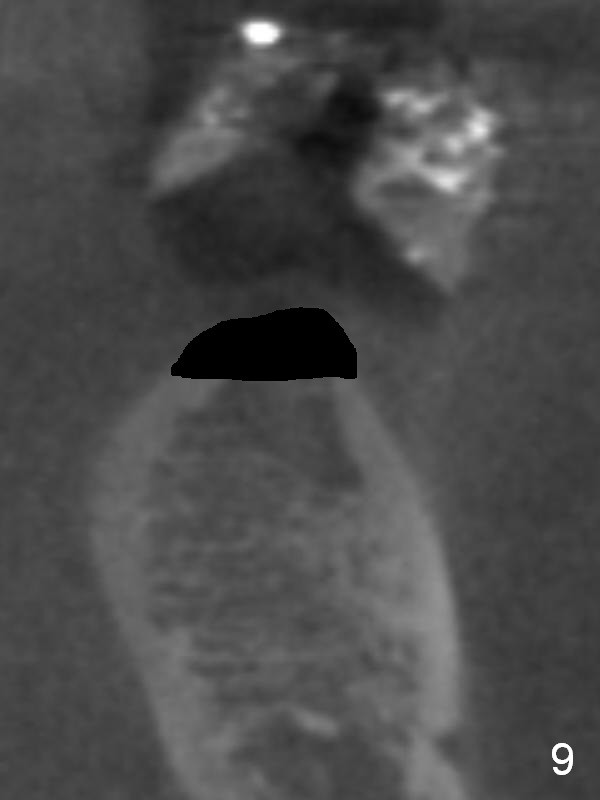

Without ridge split, the ridge top has to be trimmed (Fig.9 black area) to hold a 3 mm shorter implant (Fig.10,11).